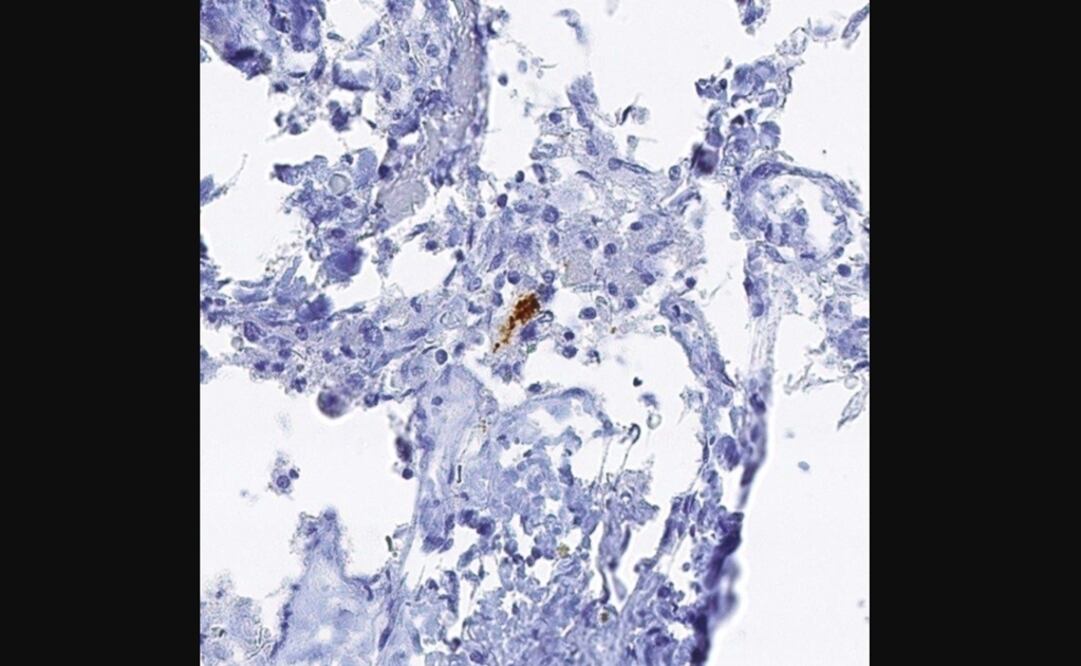

En este sentido, el estudio ha descrito un evento clave en el proceso de necroptosis que es cuando RIPK1 y RIPK3 forman una estructura filamentosa conocida como necrosoma , la cual parece que da comienzo al proceso de necroptosis.

Para explorar la necroptosis, el equipo de investigación utilizó múltiples cohortes de muestras humanas obtenidas del Programa de Donación de Cerebro y Cuerpo en el Banner Sun Health Research Institute y en el Monte Sinai VA Medical Center Brain Bank.

En primer lugar, midieron RIPK1, RIPK3 y MLKL en una región específica del cerebro que es típicamente devastada por la pérdida de células durante el avance de la enfermedad de Alzheimer. Los resultados mostraron que durante la necroptosis, estos marcadores se incrementaron en los cerebros de las personas con enfermedad de Alzheimer.

A continuación, identificaron la cascada molecular de la activación de necroptosis, con RIPK1 activando a RIPK3. Este complejo proteico se une y activa MLKL. Concretamente, el análisis de ARN y proteína reveló niveles elevados tanto de RIPK1 como de MLKL en los tejidos cerebrales 'post mortem' de pacientes con Alzheimer, en comparación con los cerebros 'post mortem' normales.